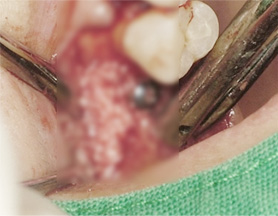

부족한 잇몸 뼈를 보충하는 뼈 이식술과

난이도 높은 상악동거상술을 진행해

안정적인 임플란트 수술을 마쳤습니다.

위 턱뼈는 아래턱뼈보다 얇고 코와 뺨 사이 빈 공간(상악동)이 있어서 임플란트를 식립할 경우 실패 가능성이 높아집니다.

상악동거상술이란 임플란트 수술방법을 시행할 때 노하우가 부족하면 임플란트 식립 후 임플란트가 빠져버리거나

입 천장 쪽에 구멍(천공)이 나는 부작용이 생기기 때문에 치과치료 중 가장 어려운 수술 중 하나 입니다.